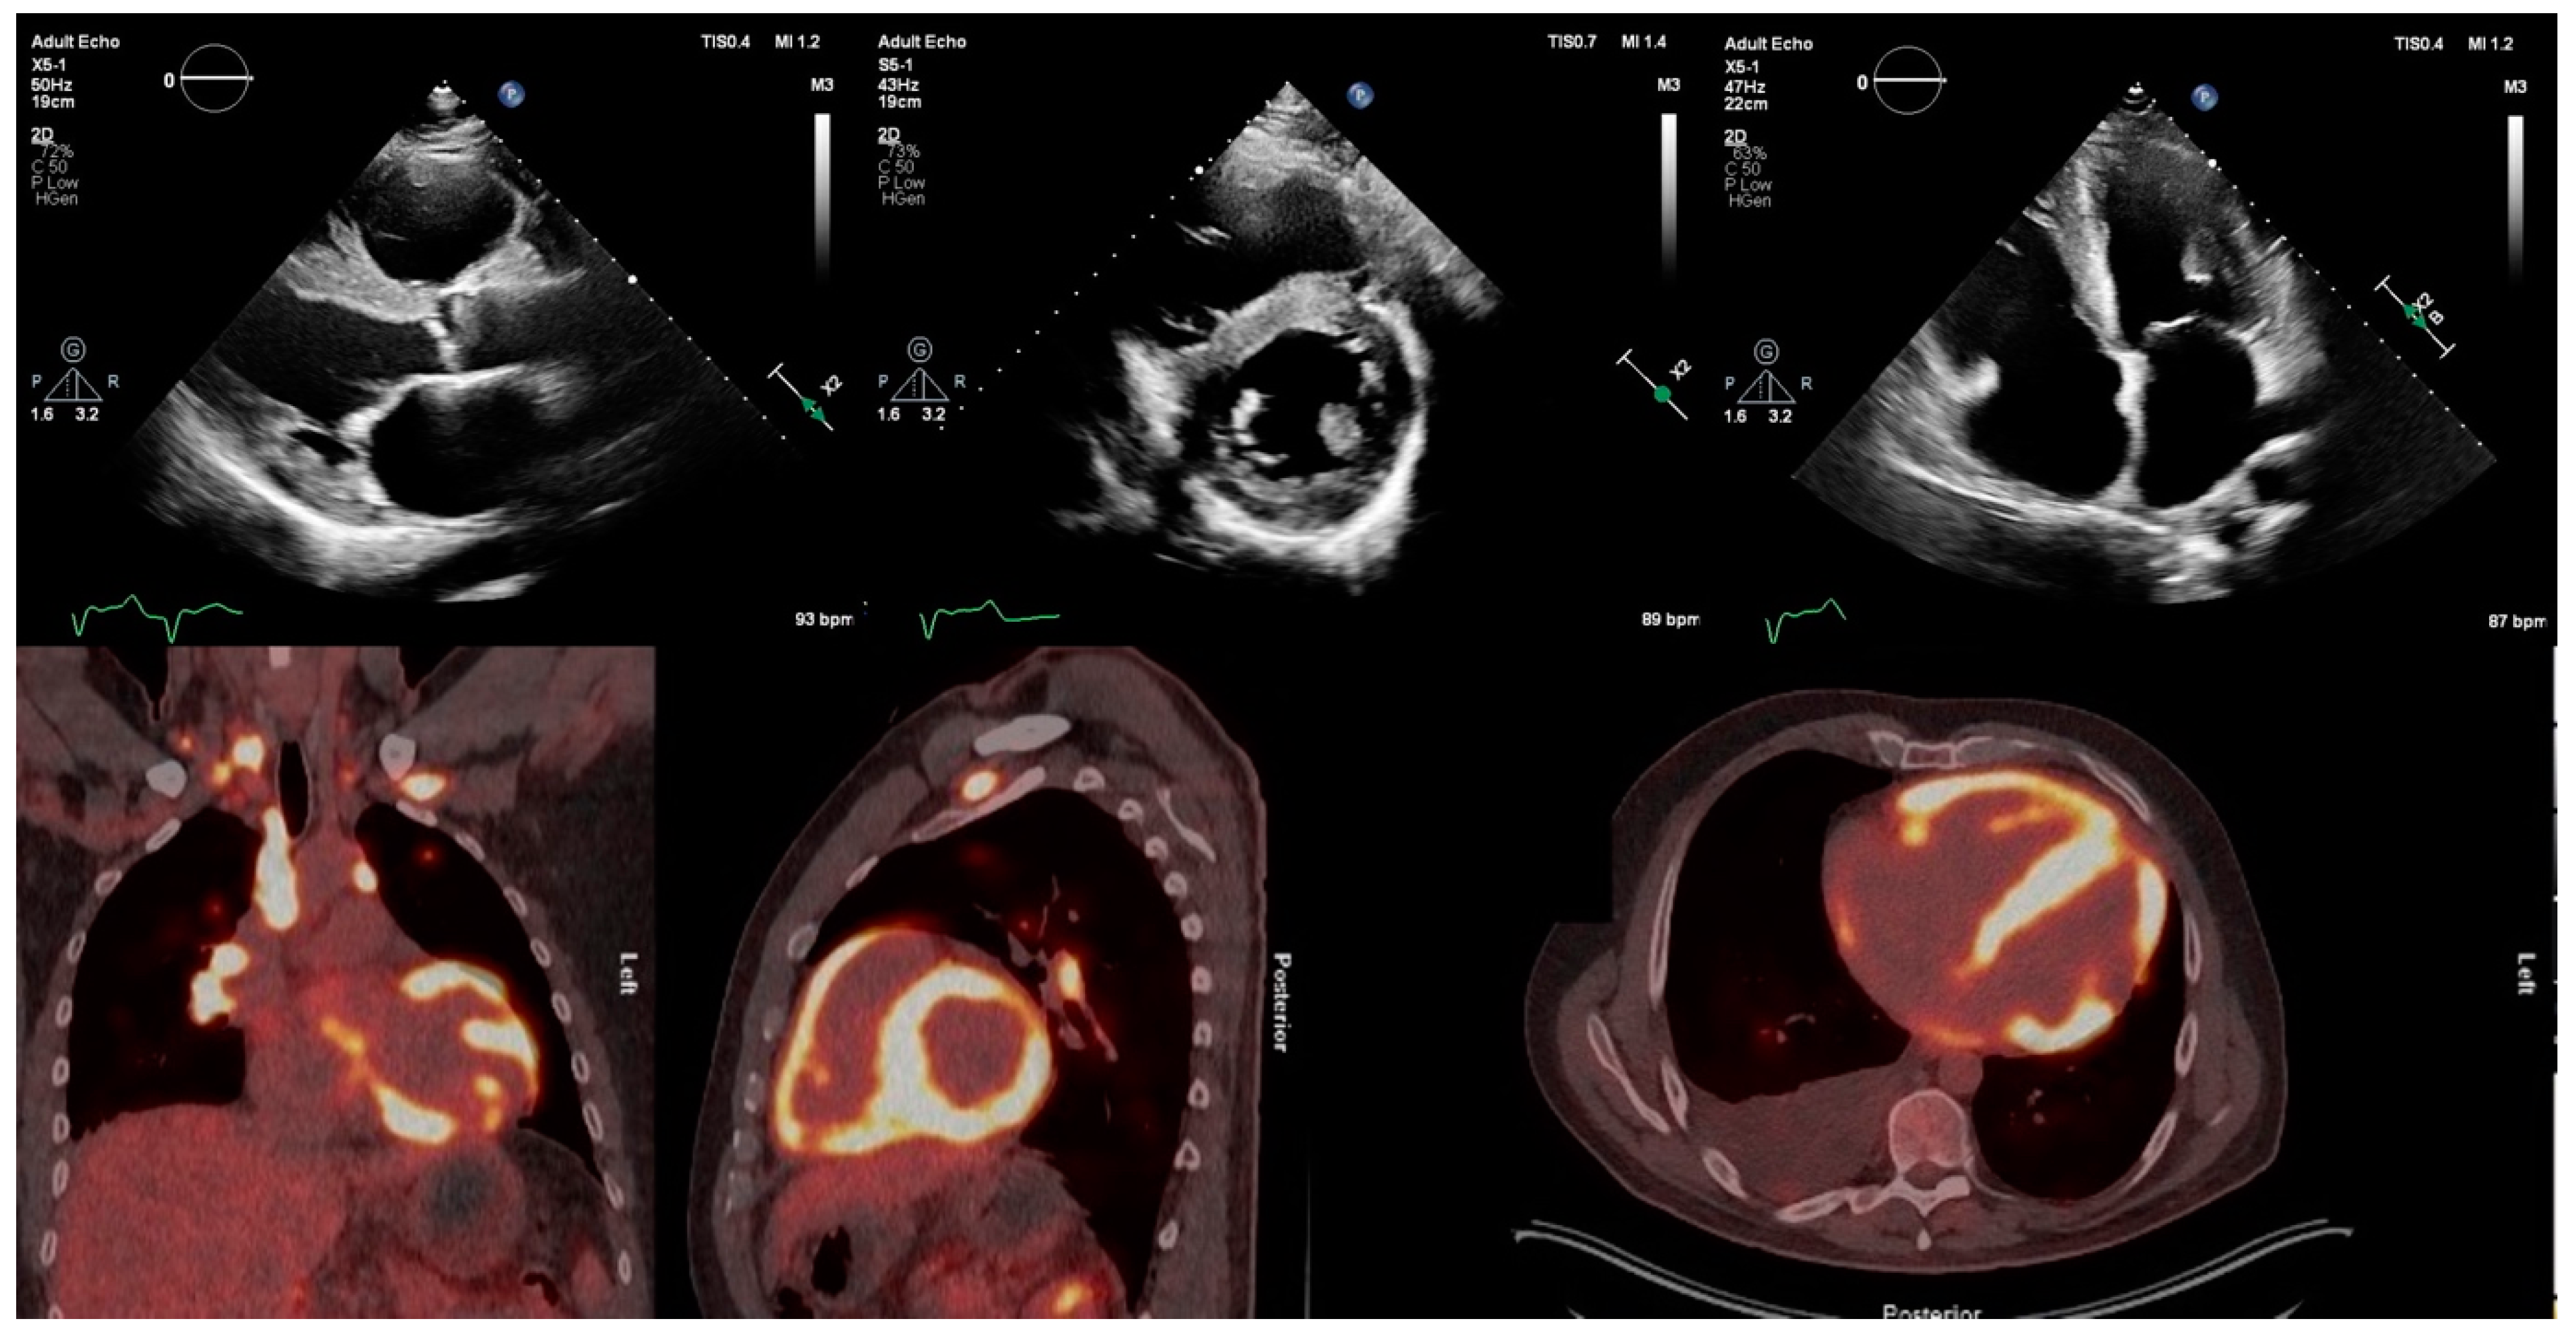

- Okafor, J.; Azzu, A.; Ahmed, R.; Cassimon, B.; Wechalekar, K.; Wells, A.; Kouranos, V.; Baksi, A.J.; Sharma, R.; Guha, K.; et al. A rare case of extensive biventricular cardiac sarcoidosis with reversible torrential tricuspid regurgitation. J. Nucl. Cardiol. 2023. [Google Scholar] [CrossRef]